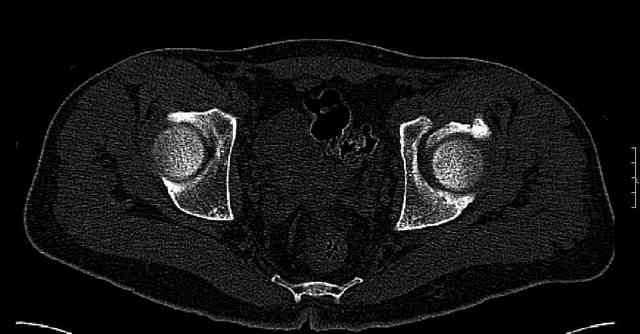

The last two images from the 3-D CT scan certainly makes the fracture look worse than the plan radiographs.

The joint is non-concentric as the head appears to be either "following the caudal segment", or the dome component is displaced from the tethered head... or so it seems... and he's young... so, many fracture surgeons would recommend reduction and fixation.

So we must decide preoperatively which part is the displaced segment?

It's difficult to know from these few selected images which component of the injury (was before and now) should be deemed the "soon to be mobile"

segment. It's my best guess that it is the caudal portion and there exists a healing fracture line somewhere thru the posterior column...one image

suggests it. If true, its early healing/union should be disrupted, and the resultant fragment mobility then allows accurate reduction.

Some more images. Does it help to guess which part of the acetabulum is displaced?

Normal appearing SI joints and a healed posterior column limb... my bet's on caudal segment displacement.

The anterior element of the fracture is so low and the anterior roof arc angle must be at least 60 deg.

The posterior element is so minmally undisplaced. There is good congruence of the joint, and to top it all, 6 weeks have passed. If you consider ORIF now, I don't expect that much improvement could be accomplished. Not to mention the need for extensive approaches with their morbidity.